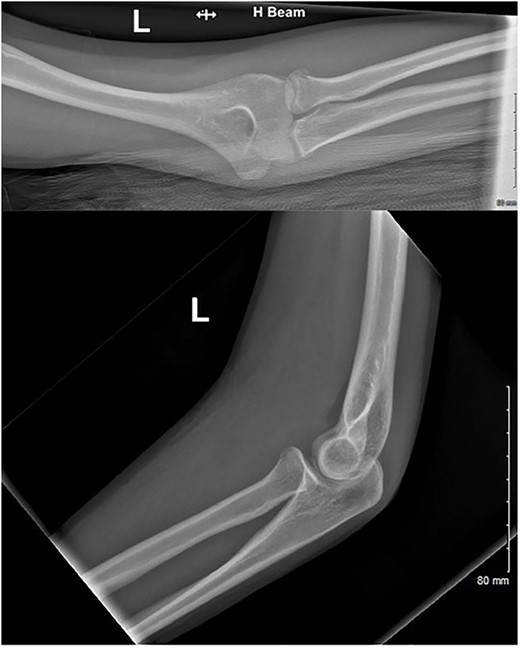

A 15-year-old right-hand-dominant female fell from her horse onto an outstretched left hand (elbow extended, forearm pronated) at an equestrian event (Video 1). The patient immediately attended the emergency department with pain and significant swelling over the medial and lateral aspect of the elbow. Radiographs were performed (Fig. 1) and an undisplaced radial neck fracture was identified. As per guidance for non-displaced radial neck fractures, the patient was discharged with a broad-arm sling and a follow-up appointment was scheduled in VFC. At VFC, the patient was discharged with a plan to mobilize as the pain allows, avoid lifting for 2 months and to return if experiencing limitation in the range of movement.

AP and lateral radiographs of the injury at first presentation to the emergency department.